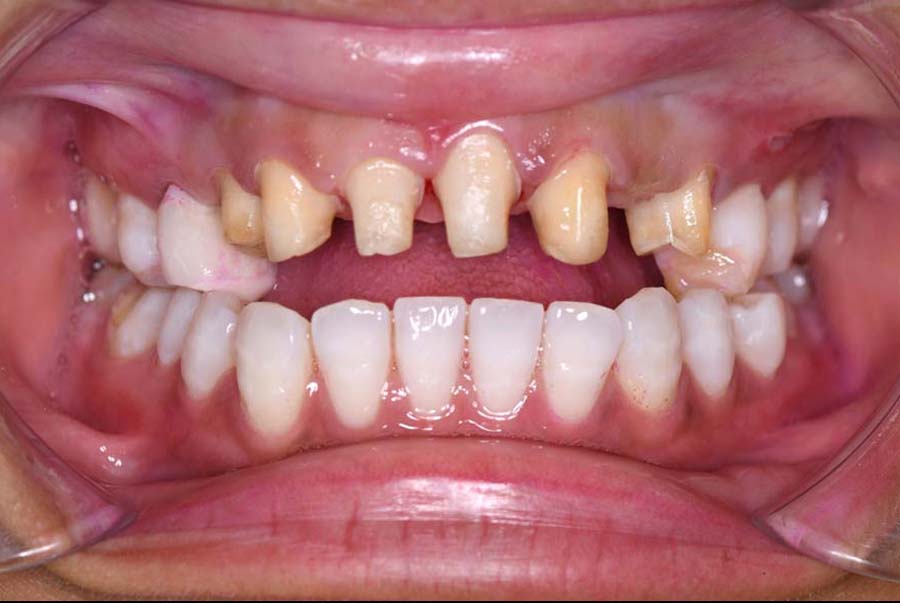

噛み合わせ治療の症例24

スプリント使用後、

補綴治療をした症例

| 治療内容 | ①スプリントを装着 ②副子を装着 ③2024年4月 口腔内反映開始 ④副子を入れた状態の所まで咬合を挙上 (バイトアップ) ⑤2024年5月 上顎前歯部8本へ仮歯(TEK) を装着 |

バイトアップ後